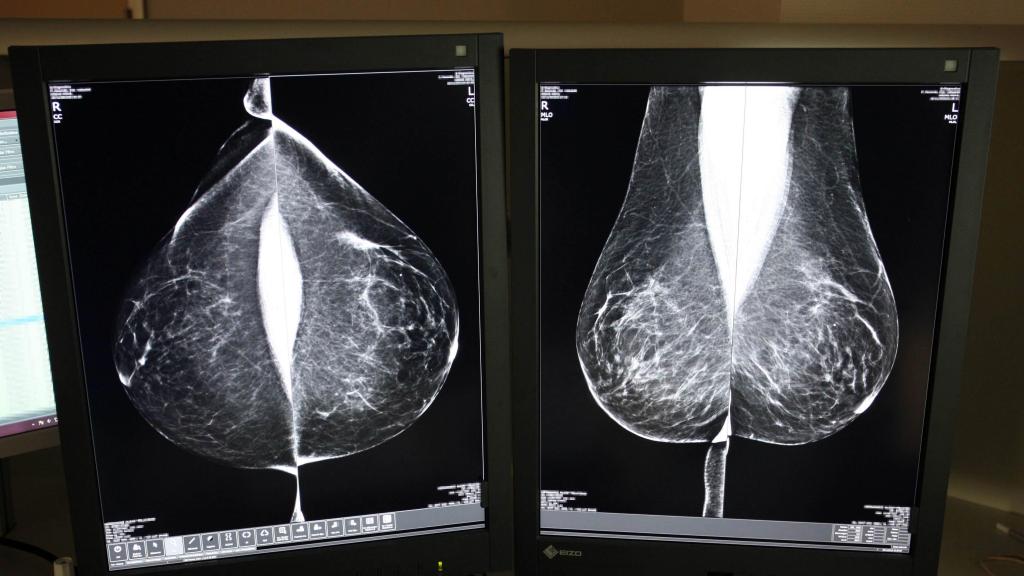

Una mamografía en el Hospital Río Hortega de Valladolid

Una mamografía en el Hospital Río Hortega de Valladolid Rubén Cacho ICAL

Desde su puesta en marcha en 1992, el programa se basa en el sistema de doble lectura, un protocolo que establece que cada mamografía sea evaluada por al menos dos radiólogos, de forma independiente, aumentando así la fiabilidad de los diagnósticos.

En 2023, último dato disponible, se realizaron un total de 122.193 mamografías, de las que 7.503 (un 6,14 por ciento) tuvieron resultado sospechoso positivo y fueron derivadas a Atención Hospitalaria para realizar el diagnóstico final. Por provincias, el porcentaje de pacientes derivadas osciló entre el 3,7 por ciento de Zamora y el 9,9 por ciento de Soria.